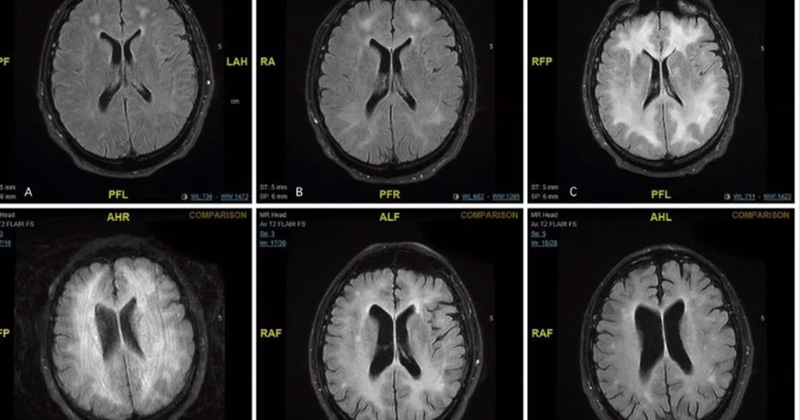

Éste es el daño que la cocaína podría causarle a tu cerebro

La Leucoencefalopatía es una afección en el cerebro en la que la materia blanca se ve severamente dañada.